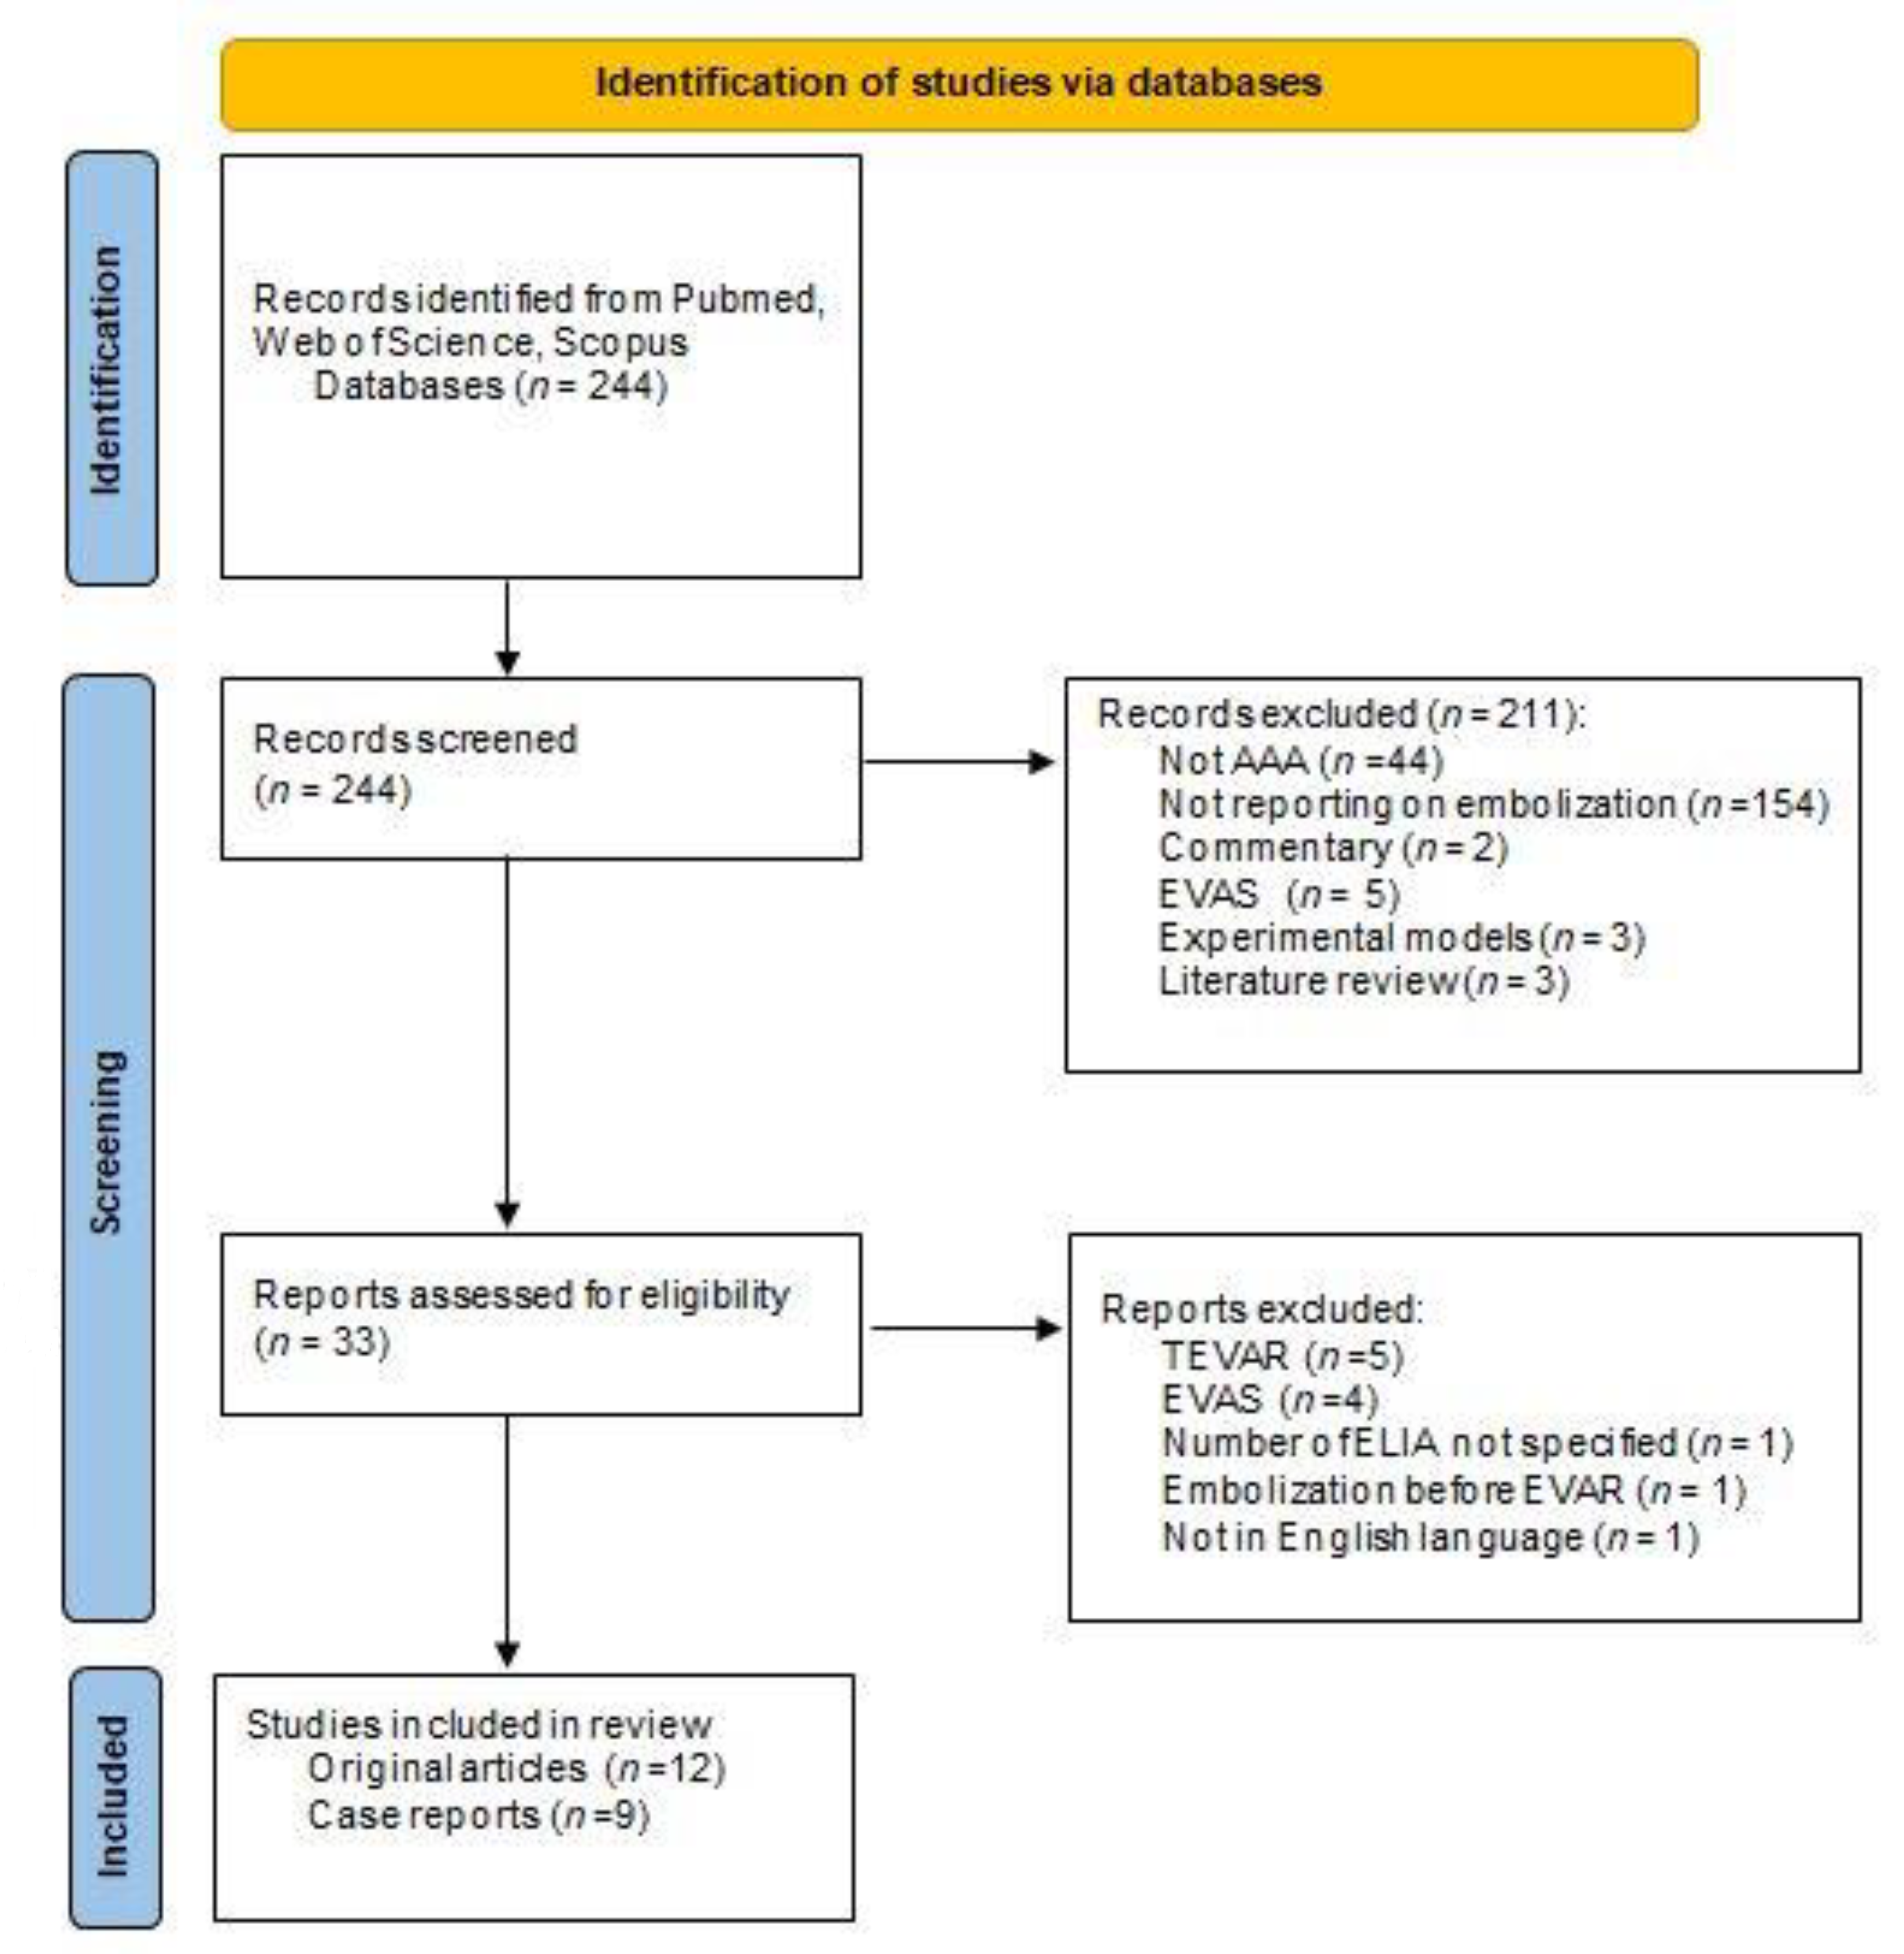

2. Materials and Methods

2.1. Data Sources and Search Strategy

2.2. Study Eligibility Criteria, Study Quality Assessment

3.1. Search Results